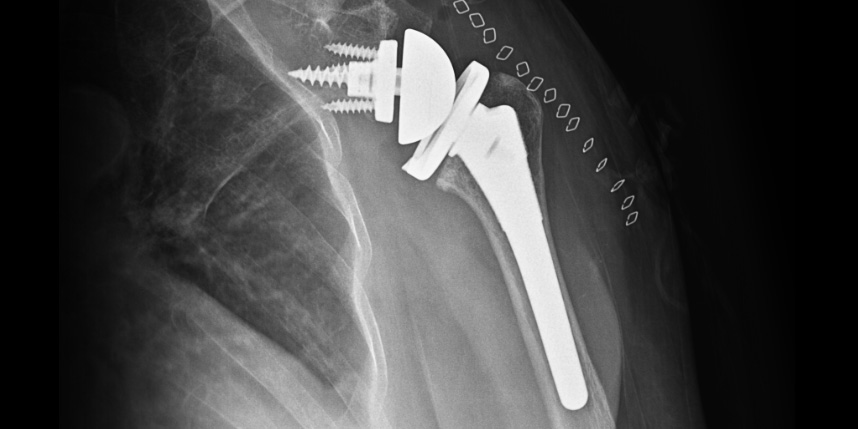

삼하게 망가져 거의 기능이 없는 관절을 제거한 후 특수하게 제작된 인공관절을 삽입하는 수술

역행성 인공관절 전치환술

역행성 인공관절 진치환술

(회전근개 심한 파열 및 관절염 진행)